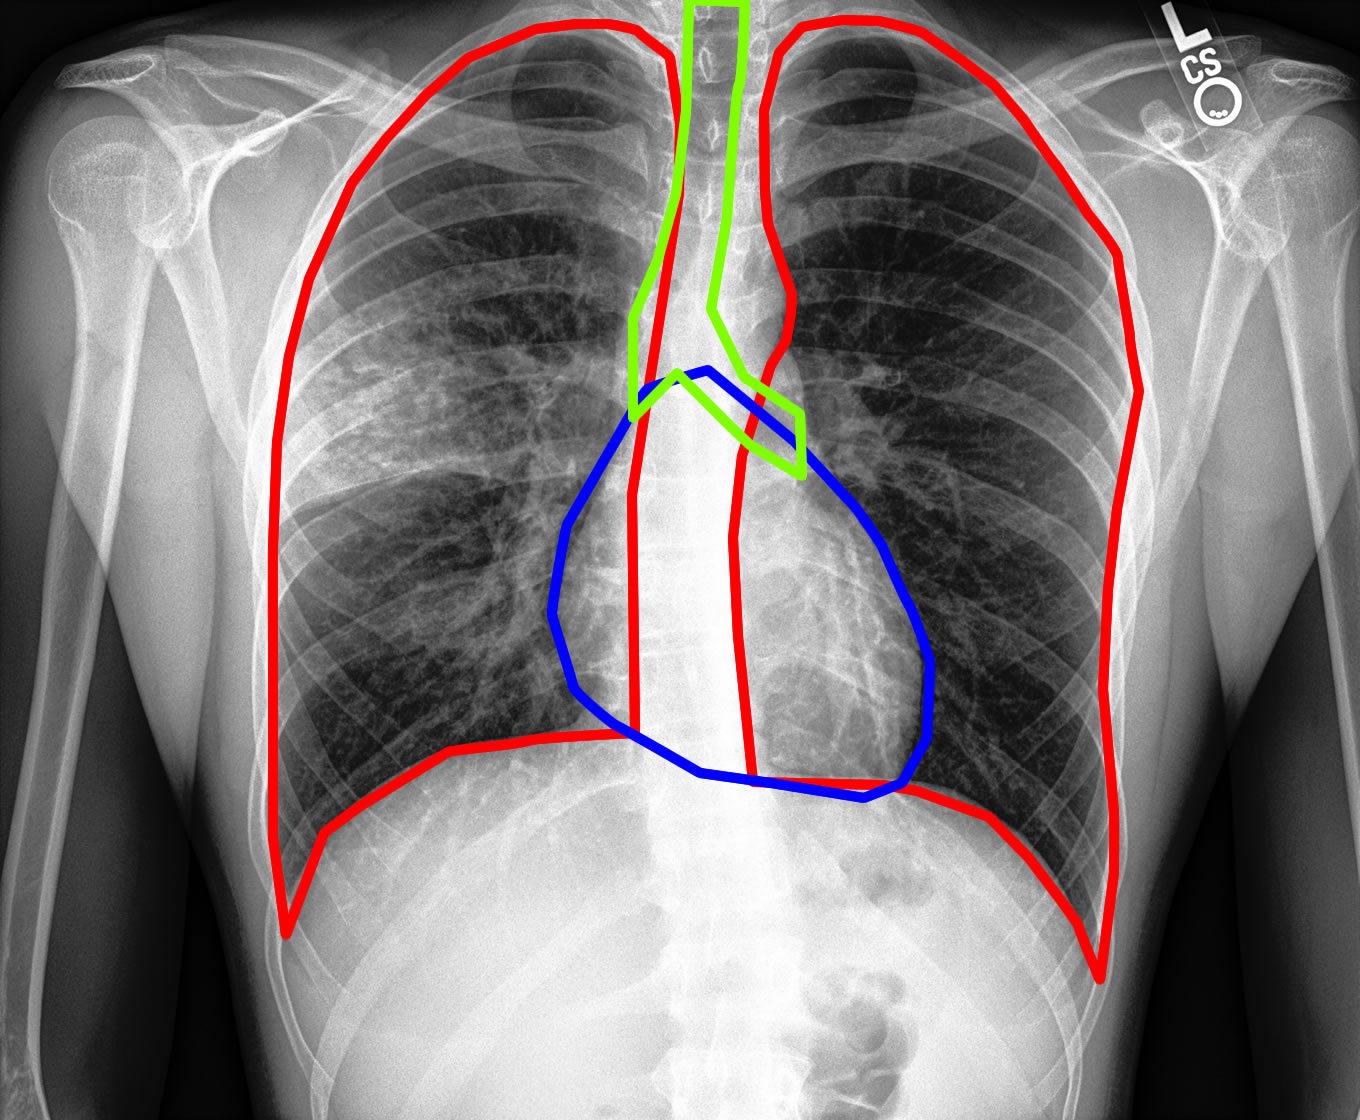

Detección de órganos

Se localizan los órganos para hacer un análisis detallado de cada uno